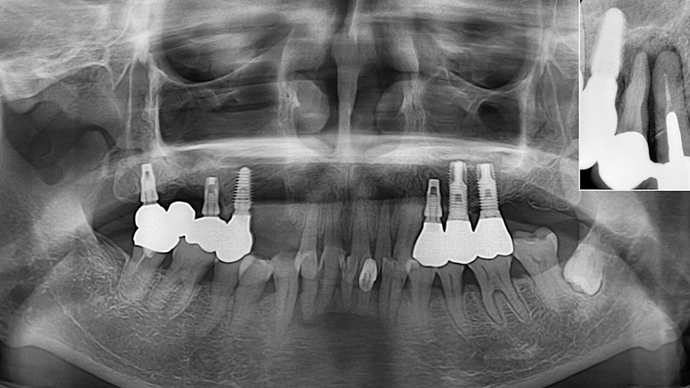

“Does guided surgery always mean flapless surgery? ”

Clinical case: R2GATE GUIDE surgery with GBR

- Courtesy of Dr. Kwang Bum Park, Korea -

Dr. Kwang Bum Park, digital guided surgery, bone regeneration, maxillary posterior, #13, #14, guided surgery, GBR, AnyRidge, i-GEN, Mega-Oss, R2GATE, R2GATE Full surgical kit

AnyRidge implant system, R2GATE Guide, R2GATE surgical kit (AnyRidge), Mega ISQ, Mega-Oss